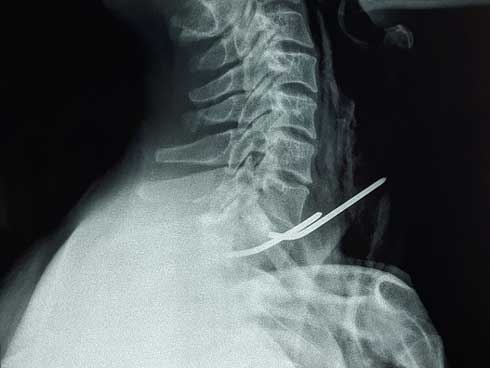

Hình chụp X-quang 2 cây đinh đâm xuyên thực quản và khí quản của bệnh nhân. Ảnh: Bệnh viện cung cấp

Qua thăm khám và làm các cận lâm sàng, như: X-quang ngực, CT-Scan, nội soi thực quản, bệnh nhân được chẩn đoán xác định dị vật vùng cổ do đinh kirschner kết hợp xương đòn đâm xuyên thực quản và khí quản. Ê-kíp bác sĩ đã phẫu thuật lấy đinh và khâu lại thực quản, khí quản cho anh P. Hiện, sức khỏe bệnh nhân ổn định, đã ăn được, dự kiến xuất viện trong vài ngày tới.